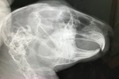

切歯もキレイ

術前検査のレントゲン

特に問題ありません。

※クリックで拡大見れます。